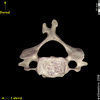

CERVICAL VERTEBRA 3

Anterior

Inferior

Posterior

Superior